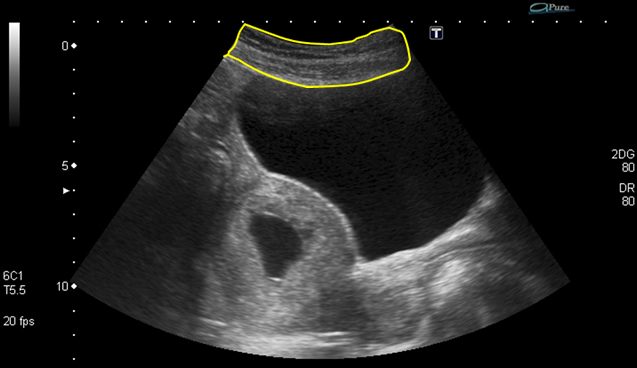

Now explore the anatomy on an ultrasound image.

Note that the urethra and the ovaries are not visible on this image.

1. Abdominal wall containing, skin, fat and muscles

2. Bowel

3. Bladder

4. Uterus

5. Vagina

6. Rectum

7. Pouch of Douglas

9. Ovaries - not visible on this image